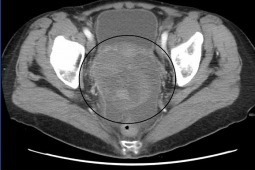

Rozpoznanie raka jajnika cechuje się niekorzystnym rozpoznaniem. Podstawowym sposobem leczenia jest cytoredukcyjny zabieg chirurgiczny i chemioterapia oparta na platynie i taksanach. Pomimo odpowiedzi na to leczenie stosunkowo szybko u znacznej części chorych dochodzi do wznowy choroby. Mediana przeżycia wolego od progresji (PFS- progression-free survival) wynosi 16 miesięcy. W dwóch badaniach – GOG-218 i ICON-7 wykazano, że zastosowanie bewacyzumabu i chemioterapii jako leczenia podtrzymującego korzystnie wpływa na wydłużenie PFS. Badania te pokazały, że w rozwoju raka jajnika kluczową rolę pełni proces angiogenezy. Prezentowana praca bada wpływ zastosowania inhibitora kinazy tyrozynowej – pazopanibu w leczeniu podtrzymującym chorych na raka jajnika.